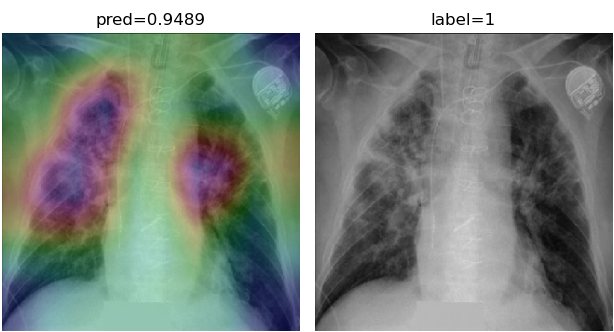

To overcome the aforementioned issues and force the model’s attention to the correct regions of interest (ROIs), we introduce the COVID-CXNet. Our model is initialized with the pretrained weights from CheXNet. A dataset of 3,628 images, 3,200 normal CXRs and 428 COVID-19 CXRs, are divided into 80% as training-set and 20% as test-set. Batch size is set to 16, rather than 32 in previous models, regarding memory constraints. Grad-CAMs of the COVID-CXNet for random images are plotted in Fig. 15.

Refer to caption

Figure 15: Grad-CAM visualization of the proposed model over sample cases

More Grad-CAMs are available in Appendix A. Heatmaps are more accurate than previous models, while an accuracy of 99.04% and an f-score of 0.96 are achieved. Table 3 is the confusion matrix of the proposed model.